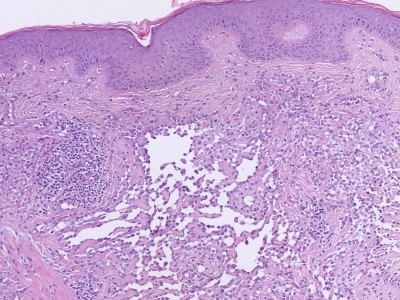

![Histologie angiosarcoma (click on photo to enlarge) [source: Nephron - Wikimedia - Creative Common License 3.0] Histologie angiosarcoma](../../../images/angiosarcoma-2z.jpg) |

![Histologie epithelioid angiosarcoma (click on photo to enlarge) [source: Kevin Kwee / Afdeling Pathologie MUMC] Histologie epithelioid angiosarcoma](../../../pacoupes/thumbnails/epitheloid-angiosarcoom.jpg) |

![Histologie epithelioid angiosarcoma (click on photo to enlarge) [source: Kevin Kwee / Afdeling Pathologie MUMC] Histologie epithelioid angiosarcoma](../../../pacoupes/thumbnails/angiosarcoom.jpg) |

| angiosarcoma |

ingescande coupe (zoom) |

Foto rechtsboven:

www.webpathology.com.

Foto linksonder: Michael Bonert (Nephron) - Wikimedia (Creative Common License

3.0).

Foto's midden en rechts onder,

hoge resolutie PA-foto's: Kevin Kwee en Afdeling Pathologie MUMC. Klik

op de afbeelding om in te zoomen.

PA:

Vasculaire proliferatie met veel mitosefiguren. De cellen zijn positief voor

markers voor vaten (CD31, CD34, FVIII-related antigen) en lymfvaten (D2-40).